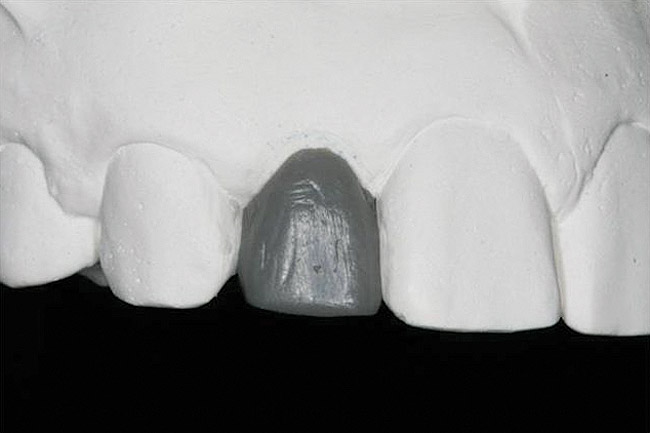

Figure 21   Gingival zenith planning: The location of the gingival zenith for this missing lateral incisor is not fully evident during initial clinical evaluation (Fig 21). Subsequent diagnostic waxing reveals the position of the planned gingival zenith (Fig 22). A thermoplastic template captures the position of the zenith and enables transferring this location to the clinical environment (Fig 23 and Fig 24). Final crown contours are defined by soft-tissue form (Fig 25).

Figure 22  Gingival zenith planning: The location of the gingival zenith for this missing lateral incisor is not fully evident during initial clinical evaluation (Fig 21). Subsequent diagnostic waxing reveals the position of the planned gingival zenith (Fig 22). A thermoplastic template captures the position of the zenith and enables transferring this location to the clinical environment (Fig 23 and Fig 24). Final crown contours are defined by soft-tissue form (Fig 25).

Figure 22